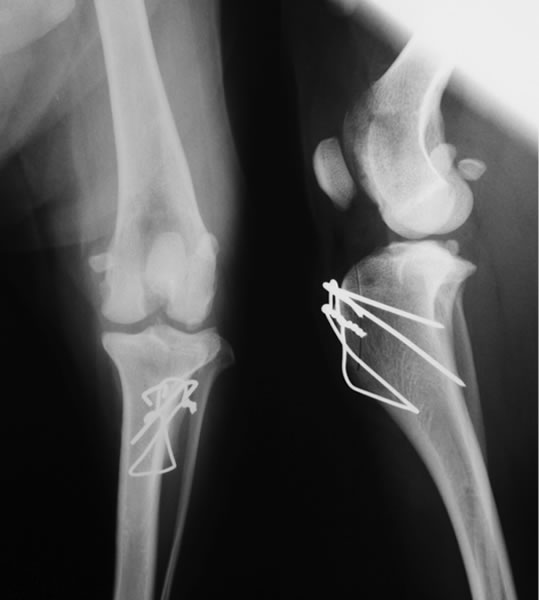

前十字靭帯断裂とは

膝関節の安定化を担っている前十字靱帯が断裂することにより、膝関節の不安定性が発現します。断裂した前十字靱帯の断端から炎症性のメディエーターが放出されるため、関節炎が起こります。

好発犬種

ヨークシャテリア、ポメラニアン、マルチーズ、チワワ、トイプードルなど。

診断

触診、レントゲン検査、関節鏡検査

治療

関節外制動法(Lateral Suture Stabilization)など。前十字靭帯と同様の働きをする位置に合成靭帯を設置し、膝関節を安定化させる手術法。